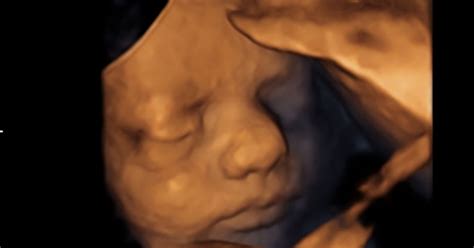

Ključna preiskava pri sumu na spontani splav je ultrazvočni pregled, ki ugotovi, ali je otrok v maternici in če še živi. Če otroka ni v maternici, pride v poštev ektopična nosečnost (nosečnost izven maternice) ali pa je že prišlo do popolnega spontanega splava. Ultrazvok lahko potrdi tudi vrste spontanih splavov, kot je izostali splav ali prazna gestacijska vrečka.